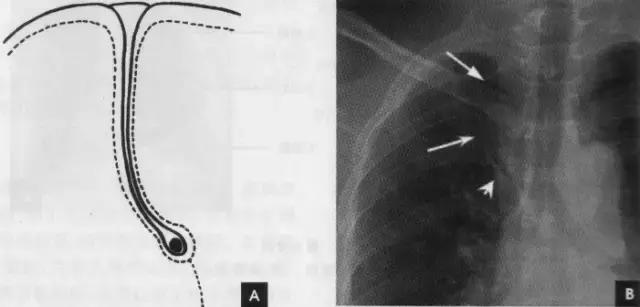

(1)奇叶系因奇静脉位置异常所致,发生率约为0.5%。胚胎发育早期,奇静脉跨于右肺尖,在肺曩上发育时,奇静脉应下移至肺尖内侧,最后固定于右侧纵隔内肺根上方。若这种滑移动作受阻,奇静脉即嵌入右肺上叶肺尖部,壁胸膜和脏胸膜也随之陷入,所以奇副裂由四层胸膜所组成,即两壁胸膜和脏胸膜,被奇静脉分隔的右肺上叶内侧部分称为奇叶。后前位胸片上,奇副裂呈细线状影,由右肺尖部向内、下走行至肺门上方,终端呈一倒置的逗点状,是奇静脉断面的垂直投影(如下图):